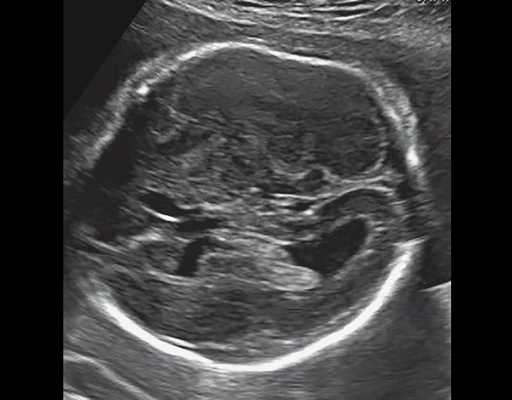

б) Узкая грудная клетка.

в) Узкая грудная клетка.

| Набл. 4. 26,5 нед? | БПР - 22,6 нед. ОГ - 22,6 нед. Форма - трилистник (рис. 4а). Боковые желудочки - 22 мм, высокий лоб, расширенный родничок, сагиттальный шов (рис. 4б). | Торакоабдоминальное соотношение - 65,7% (рис. 4в). Окружность груди - среднее для 23 нед. Колоколообразная форма. | ДБ - 23 мм (51% от должной). Остальные кости - 50% для 15-17 нед. Нормальная установка пальцев кисти (рис. 4б). | Уплощенные тела поясничных позвонков (рис. 4г). |

Полученные результаты свидетельствовали о наличии у всех исследованных плодов скелетных дисплазий с гипоплазией грудной клетки. В дополнение к этому в наблюдении 4 наличие формы головы плода в виде трилистника позволило нам установить диагноз ТД II типа.

УЗИ позволяет выделить группу скелетных дисплазий плода с сужением грудной клетки, являющимся одним из важных прогностически неблагоприятных признаков независимо от нозологической формы остеохондроплазий. Во всех представленных нами случаях у плодов отмечены микромелия и гипоплазия грудной клетки (окружность грудной клетки была менее 5% для гестационного срока, а торакоабдоминальное соотношение было в пределах 56,6-67,6%).